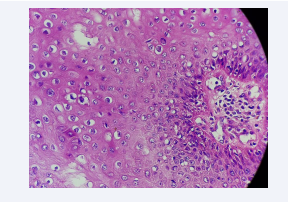

Anatomopathological study revealed a polyploid lesion lined by an ortho-keratotic hyperkeratosis. Koilocytes were found in the superficial layers of the epidermis [Figure 4].

Morphological aspect at high magnification showing  koilocytes.

Figure 4: Morphological aspect at high magnification showing koilocytes.

Concluding to a Buschke Lowenstein tumor.

It is a perfectly limited squamous tumor characterized by epithelial hyperplasia, sometimes pseudoepitheliomatous, hyperacanthosis, hyperpapillomatosis and koilocytes which are pathognomonic markers of HPV infection, however their presence is not constant. The basement membrane remains intact as evidence of the benignity of the tumor despite its malignant behavior. Careful histological examination is crucial to exclude transformation to SCC [10].